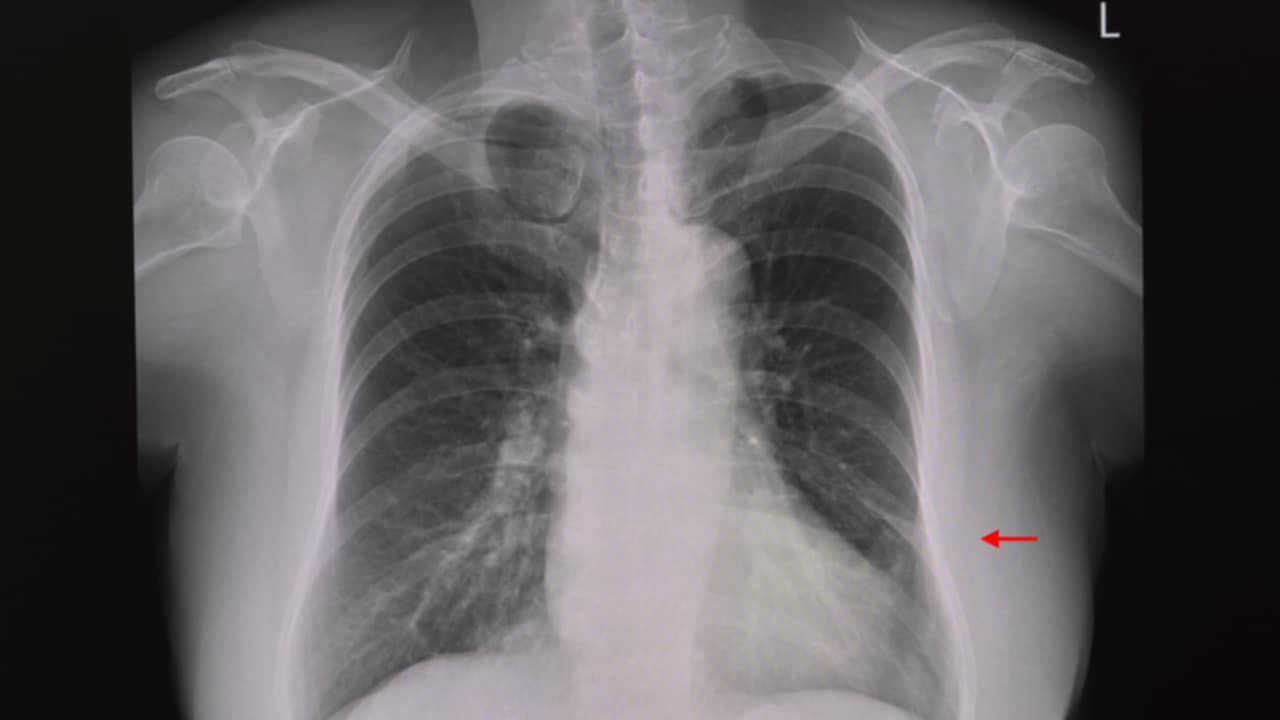

La diagnosi di solito richiede una valutazione clinica approfondita accompagnata da una radiografia del torace. Tuttavia, per confermare il sospetto diagnostico e valutare la gravità della condizione, possono essere utilizzate ulteriori tecniche, come la tomografia computerizzata, la broncoscopia, l’ecografia e l’ossimetria. La broncoscopia è particolarmente utile poiché consente di visualizzare eventuali ostruzioni e, se necessario, rimuovere il blocco.